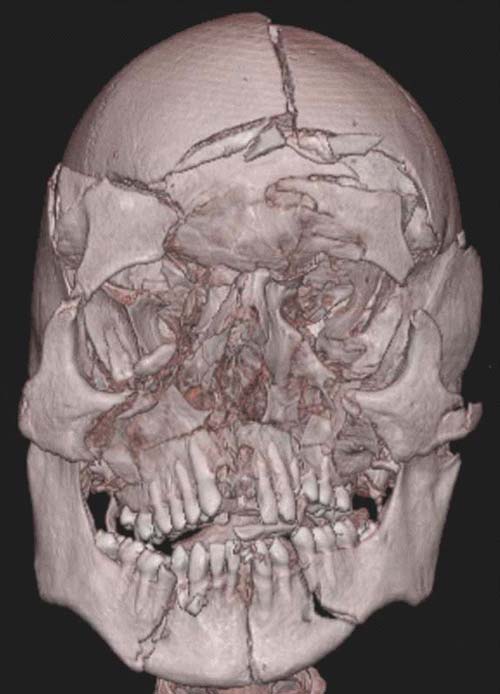

Blunt injuries to the head can be differentiated into two groups: (1) impact injuries and (2) injuries due to a rapid change in velocity (acceleration and deceleration). Of the first group, soft-tissue injuries of the scalp and facial musculature (lacerations, abrasions, and contusions), skull fractures, cerebral contusions/lacerations, intracerebral hemorrhages, and epidural hemorrhages are notable. The second group, namely the change in velocity, which is, for instance, encountered in shaken baby syndrome and vehicle accidents, typically presents with subdural hematomas and diffuse axonal injuries. The latter is discussed in Chapter D3.3.4 on craniocerebral trauma. Although the topic of cerebral trauma is discussed in detail in Chapter D3.3, the importance of skeletal lesions to the head in blunt trauma deserves brief mentioning.

Facial fractures are a common finding in clinical forensic medicine and in forensic pathology. They usually arise due to direct trauma as in vehicle accidents, falls onto the face (often seen in intoxicated persons), or, more frequently, in fights and scuffles.

Of these, the fracture of the nasal skeleton is the most frequently encountered. Although generally a self-limiting lesion with little or no danger to the individuals' life or general health, nasal fractures can lead to the suspicion of an involvement of a third party in otherwise inconspicuous conditions. If an otherwise unharmed body of a young man is found in a locked flat with signs of a nasal fracture, then further investigations must be undertaken, even if the presence of a perpetrator at the time of death can be excluded. As the nasal fracture is a possible sign of a prior fight, an autopsy must be performed to examine the possibility of further, externally unseen lesions. However, a nasal fracture may be missed at external inspection. As a dissection of the face leads to disfigurement, the pathologist often refrains from this procedure. Therefore, the nasal fracture may even be missed after an otherwise complete autopsy has been performed. Postmortem multislice computed tomography (MSCT) easily detects such possibly telltale fractures (Figure D3.2.7).

Other frequently seen fractures of the facial bones concern the eye sockets and can arise due to direct blunt trauma due to punches or impact from a flying object such as a ball. These blow-out fractures are typically located at the medial and basal wall, where the bone is extremely thin [6,7]. However, eye socket fractures can also arise due to indirect trauma, such as in cases of falls with an impact to the back of the head as a contrecoup lesion [8]. Whereas these indirect fractures, typically located at the roof of the eye socket, are formed by a negative pressure in the fossa anterior, the opposite may also give rise to fractures of the orbita ceiling [9]. Such a rapid positive pressure can be achieved by gunshots to the skull.

As is well known from clinical medicine, mid-face fractures can also extend over the maxilla and the zygomatic bone (Figure D3.2.8). These fractures arise from a direct impact to the face. Depending on the involved structures, these fractures are classified as Le Fort I-III. This classification can be difficult, especially in cases of vehicle accidents, where, due to the massive damage, multiple fractures are often seen. In such cases, the Le Fort classes overlap (Figure D3.2.9). Mandibular fractures occur due to punches, falls, and vehicle accidents, to name just a few mechanisms. Direct fractures are seen paramedially, whereas indirect fractures are mostly located in the region of the joint and the mandibular body.

Postmortem imaging can display such possibly telltale injuries in a rapid and nondestructive manner, thus sparing the face from further disfigurement or the pathologist from missing a potentially important finding.

Whereas in cases of sharp trauma the type of inflicting instrument may be discerned in most cases, this is not true for all contusions and lacerations of the scalp. For instance, it is obviously of utmost importance to distinguish between scalp contusions, due either to a fall or to a blow with an instrument. The fracture pattern of the skull and typical cerebral lesions can solve this problem with a large degree of certainty. If the head strikes a broad, flat surface, such as the ground, the skull is flattened at the point of impact. Due to this resulting inward bending, distant areas of the skull are bent outward. Fractures do not begin at the point of impact but at the point of outbending at the external surface [10,11]. For instance, a fall with a low-energy impact to the occipital skull will therefore classically lead to linear fractures (Figure D3.2.10). If the impact of the large, flat surface is great enough, complete or incomplete circular fractures may arise around the impact point at the edge of inward and outward bending. With an even greater amount of energy, the severe inbending at the point of impact leads to stellate fractures arising from the impact center. A combination of circular and stellate fracture lines creates a distinct spider web-like fracture system. Later fracture lines will not cross preexisting fracture lines, as the necessary tension is lacking in previously fractured areas. This phenomenon, also known as the "Puppe-rule" can help assess the timing of skull injuries when more than one impact point is seen.

If the impact occurs with high energy and a small surface area, i.e., in blows with hammers, the result is a small, depressed skull fracture (Figure D3.2.11 and Figure D3.2.12). Here, the brain is generally only affected in the immediate vicinity of the impact. A blow to the head (i.e., the occiput) will therefore mainly result in a cerebral injury to the occipital brain regions. Several blows to the head can obscure the small, depressed fracture due to the severe destruction of the concerned skull region. By contrast, a fall from great height or from an upright position onto the ground will lead to a completely different fracture pattern and cerebral injury (Figure D3.2.13). Here, linear or, if the energy involved is great enough, circular fractures are commonly encountered. Simple linear fractures are, however, also seen in (lowenergy) blows to the head. In these cases, the plain radiograph of the skull does not suffice to distinguish between a blow and a fall. Here, postmortem MSCT imaging can deliver quick and reliable results. By enabling the visualization of the brain, coup-contrecoup lesions can be detected. This constellation of impact-near and impact-far injuries is often seen in falls. They are an absolute rarity in cases of homicidal blows to the head. Thus, by visualization of the brain, the pathologist may be able to discern between a blow and a fall even if the external wound morphology may be obliterated or hidden (e.g., due to secondary animal involvement such as ants). The cerebral injuries inflicted by blows and falls are discussed in detail in Chapter D3.3.